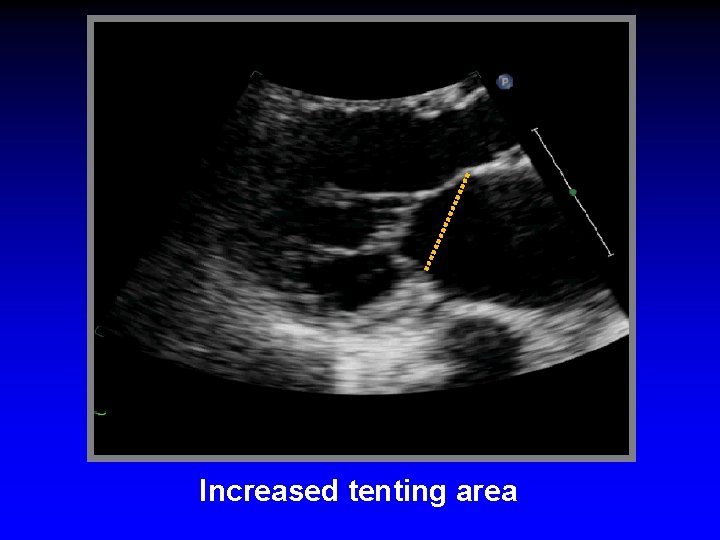

Functional Mitral Regurgitation • Global LV dysfunction • Regional LV dysfunction • Sphericity of LV • Excessive pap muscle displacement • Decreased overlap of leaflets • LA enlargement • Loss of systolic mital anular contraction • Increased “tenting” area • Delayed activation of P-M pap muscle (dyssynchrony)

Ischemic Mitral Regurgitation C B A D Mitral leaflets are tented apically Mitral annulus is enlarged (A-B = 45 mm) Mitral coaptation depth is increased (C-D = 13 mm)

Basal cord tents anterior leaflet (“seagull sign”) Increased tenting area

Increased tenting area

Ischemic Mitral Regurgitation Mechanisms • Dislocation of papillary muscles - Papillary muscles dislocated toward apex - Apply traction to chorade - Chordae tendinae lack elasticity • Increased tenting length and area • Antero-posterior dilatation of the MV annulus • Kinetics of MV annulus during cardiac cycle • Intraventricular synchrony/dyssynchrony • Atrio-ventricular synchrony

Ischemic Mitral Regurgitation Mechanisms • Dislocation of papillary muscles • Increased tenting length and area 1. Anterior MI displacement of the 2 pap muscles in the global LV enlargement 2. Posterior MI displacement of the postero-medial pap muscle responsible for an asymmetric tethering • Antero-posterior dilatation of the MV annulus • Kinetics of MV annulus during cardiac cycle • Intraventricular synchrony/dyssynchrony • Atrio-ventricular synchrony